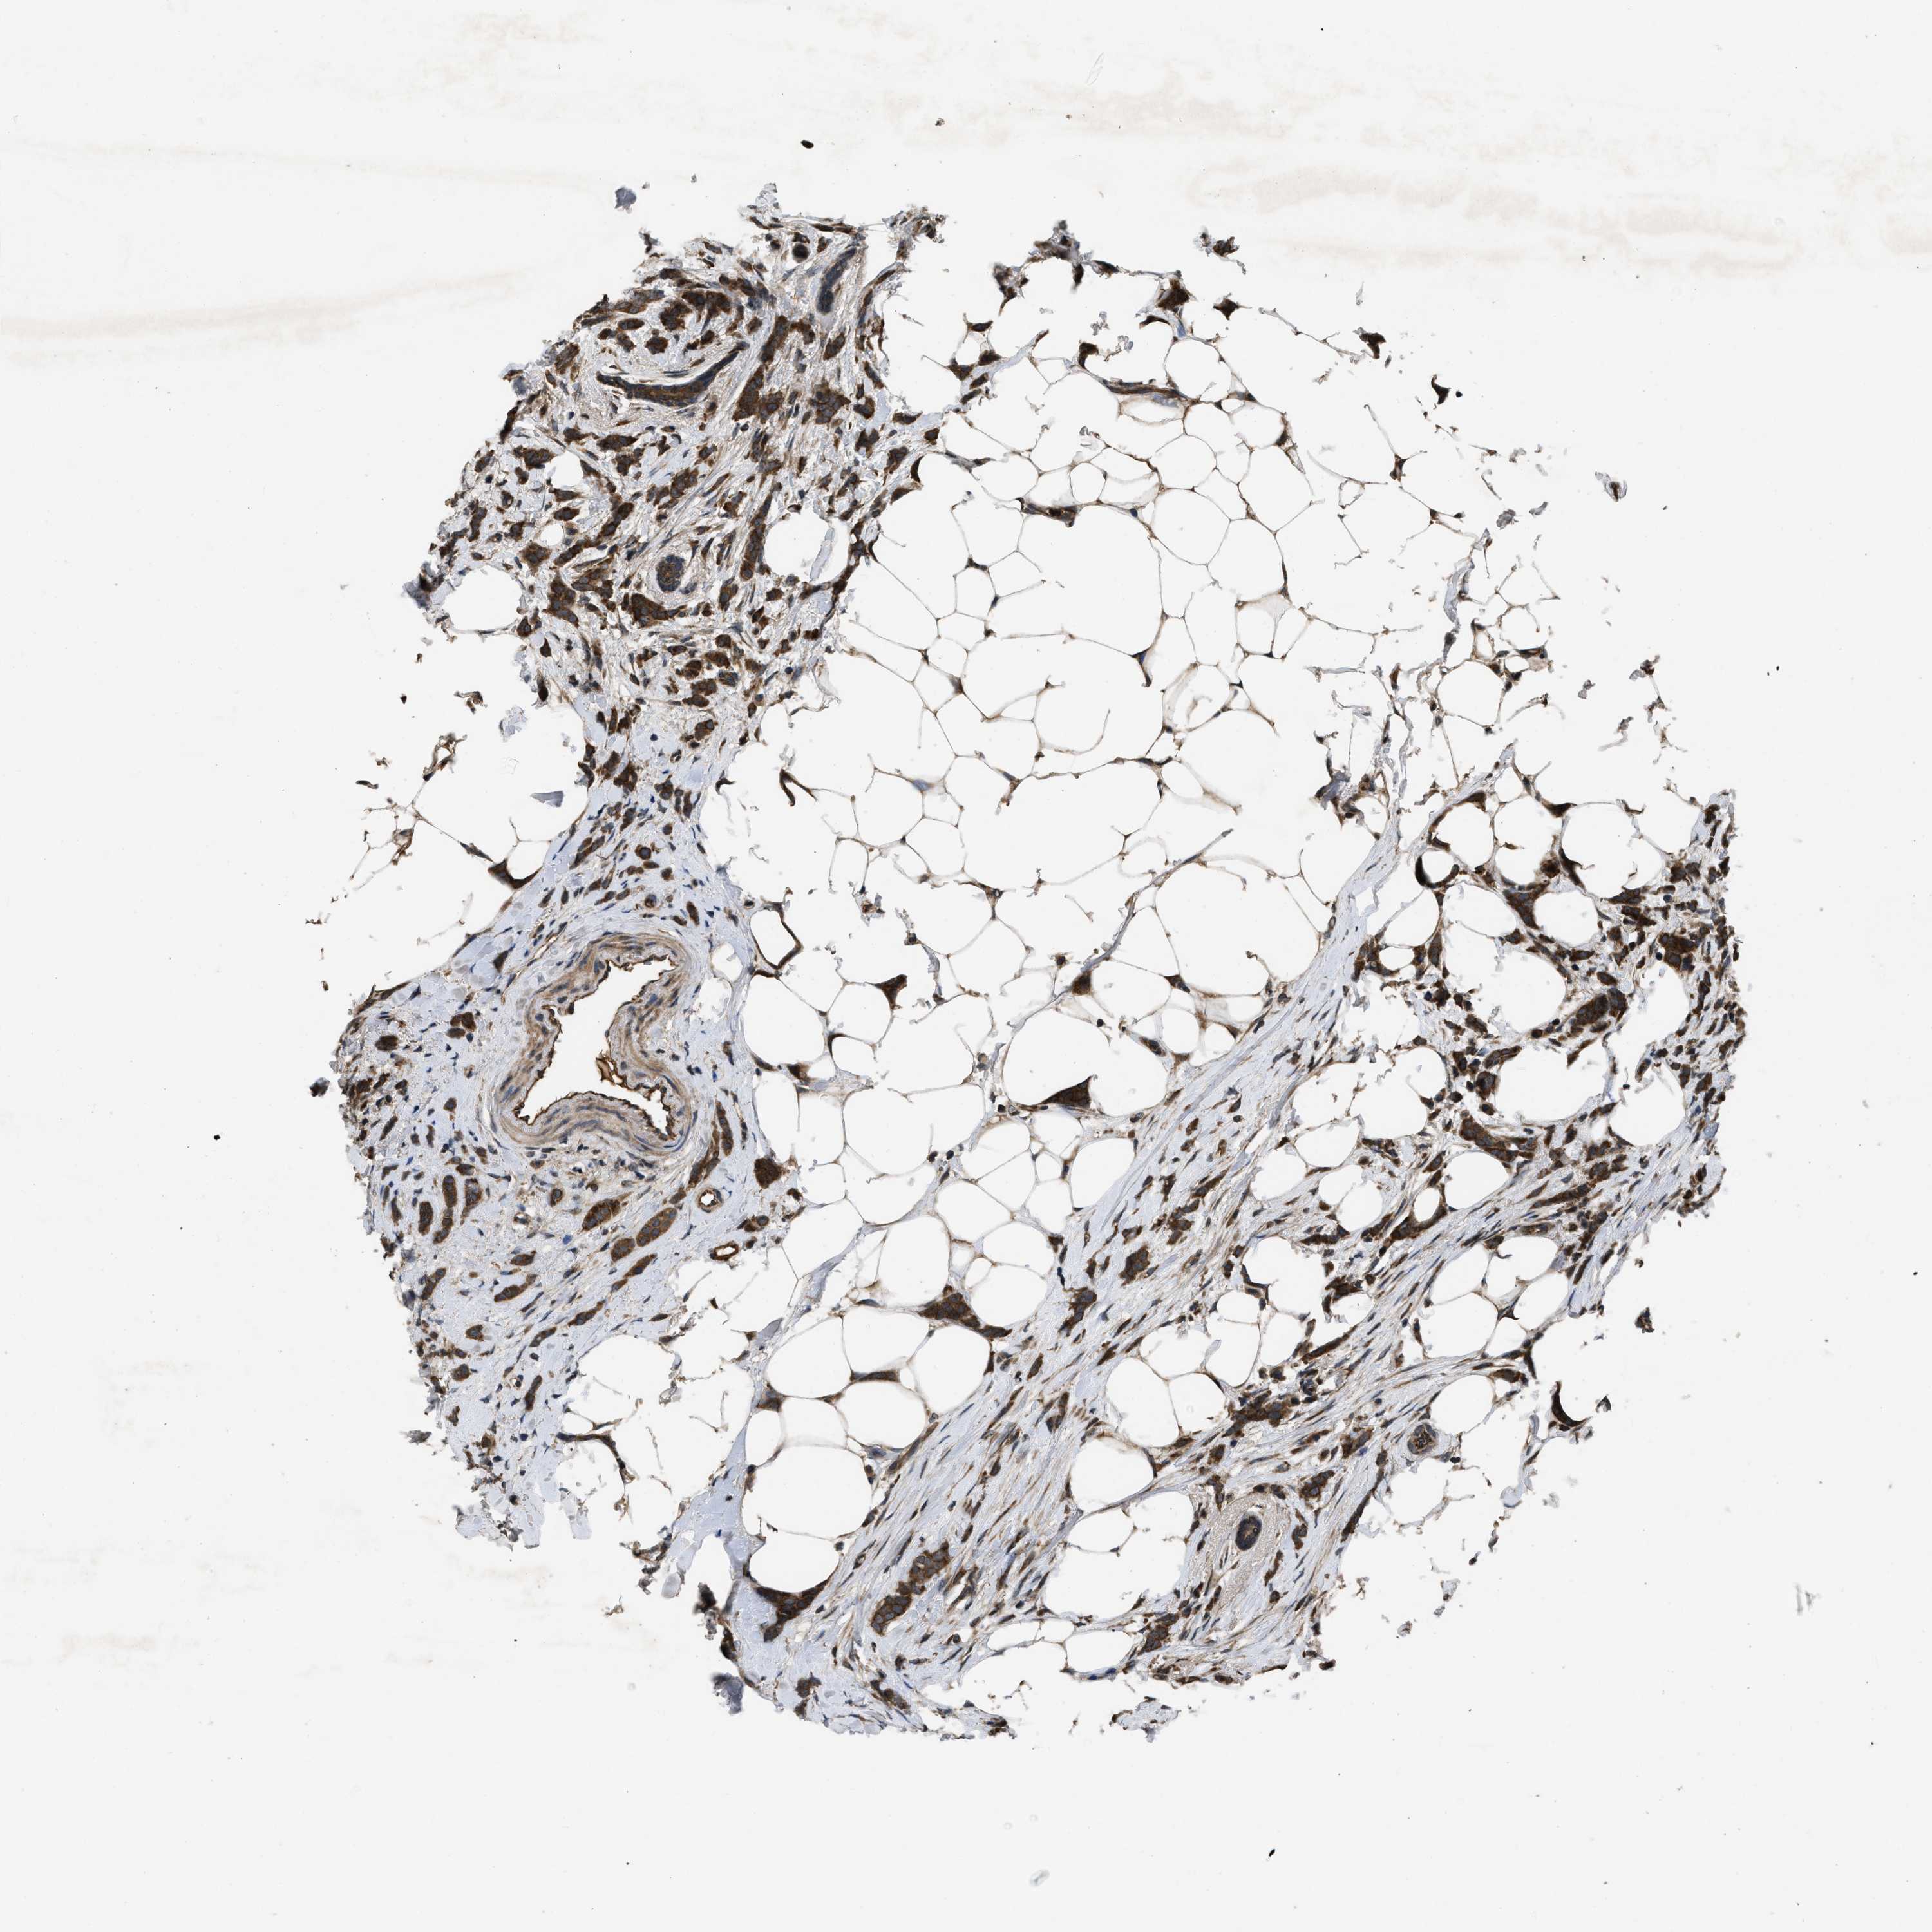

CANCER BREAST CANCER Show tissue menu

Breast cancer

Human cancer